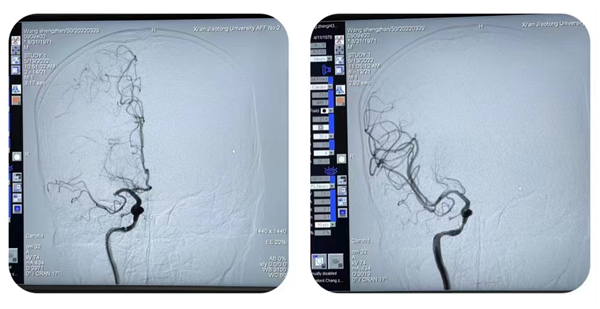

首先,张桂莲主任团队为一例保守药物治疗效果欠佳、反复发作脑梗死、慕名前来我院的患者,实施了左侧大脑中动脉支架植入术,并对患者麻醉苏醒后状态进行了直播。颅内症状性动脉狭窄因颅内血管腔大壁薄、操作复杂、技术要求高、手术风险大等特点,属于神经介入高难度手术,是优秀介入团队的标志。张茹副主任从手术指征、手术准备、手术操作、术后护理等方面进行了详细的剖析和讲解,手术全程操作流畅,术后患者恢复良好,并于术后第二天顺利出院。

图片1_副本.png